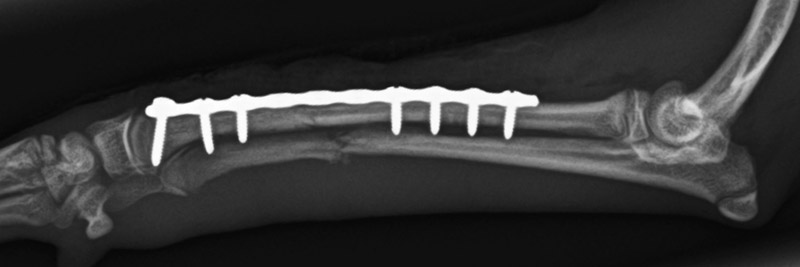

橈尺骨骨折

トイプードル(8カ月齢)

ボール運動中に転倒

手術前

手術後